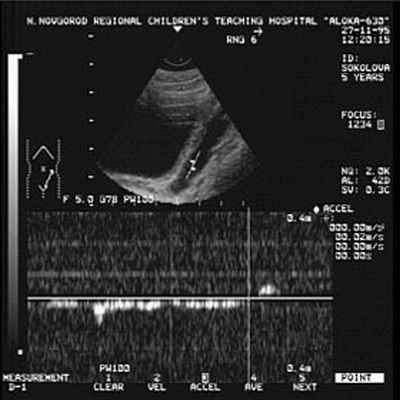

Заподозрить наличие ПМР можно данным УЗС, причём достоверность данных возрастает при использовании допплерографии (рис. 1), но наибольшей информативностью обладает рентгенологический метод - микционная цистография (рис.2). При цистографии контрастное вещество по тонкому катетеру, безболезненно вводится в мочевой пузырь и на рентгеновских снимках, выполненных в покое и при мочеиспускании отчётливо определяется проникновение контрастного вещества в мочеточники и в полостную систему почки (чашечно-лоханочную систему). Дальнейший план обследования зависит от выявленной патологии и может включать: лабораторное обследование, экскреторную урография, статическую и динамическую сцинтиграфию почек, уректро-цистоскопию, уродинамическое обследование, консультация невролога.